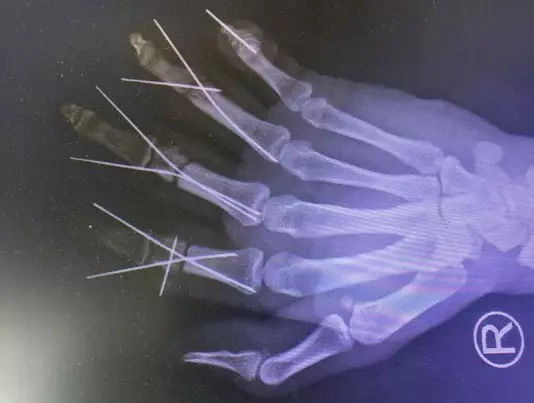

“伤情比较重,第3和第4根指头血管条件特别不好,我们截掉了损伤较重的一段血管后,长度就不够了,所以我们赶紧从患者前臂取血管,取了大概6公分的血管分成了3段分别进行移植,这样才成功接活了断指。”唐洪伟医生说。

接近12个小时过去了,唐洪伟手术小组克服了术中遇到的种种状况,终于成功完成了手术,取得了“战役”的胜利,让患者的4根手指“失而复得”!

目前,严涛的断指已全部再植成活,血运良好,仍在恢复中。